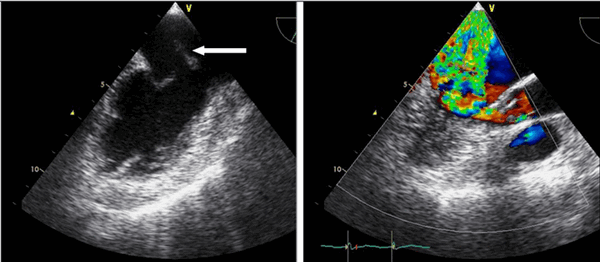

Двумерная эхокардиография

Двухмерная эхокардиография может выявить структурные аномалии протеза, такие как фистулу, вегетации, тромб, или дегенерацию ткани протеза. Однако ее чувствительность к сердечной дисфункции протеза затрудняется трудностью визуализации структур вокруг и позади сердечного протеза. Эхо отражение от протезного материала, затухание ультразвукового луча, и несколько других ультразвуковых артефактов от протеза могут вызвать трудности в толковании. Обычно, на эхокардиографии легче изучить изображения биологического протеза, чем механического. Для выявления структурных аномалий, связанных с протезом, важно понимать характеристики протеза и хирургический метод, который был использован.

Обструкция протеза на эхокардиографии

Заболеваемость обструкции протезированных клапанов оценивается в 0,1% до 0,4% в год, в зависимости от размера клапана, его типа, расположения и адекватности антикоагуляции. Тогда как обструкция митрального механического протеза возникает чаще от тромба, причиной сужения механического протеза аортального клапана более часто является формирование паннуса. Когда работа протезированного клапана будет затруднена, происходит нарушение движения диска, шара, или уменьшается подвижность створки. Однако, это трудно выявить эти ситуации, и еще труднее оценить количественно, ограничение экскурсии на простой трансторакальной эхокардиографии. Чреспищеводная эхокардиография может в состоянии визуализировать нормальные и патологические движения протезированного клапана. Самый точный способ для выявления и количественной оценки степени обструкции протезов является допплер-эхокардиография. Допплеровское исследование должны быть выполнены датчиком с различных позиции, чтобы гарантировать, что фиксируется максимальная скорость в месте стриктуры протеза.

Кроме допплеровского отслеживания скорости, максимальный и средний градиенты давления и эффективная площадь клапана могут быть рассчитана по тем же формулам и уравнениям, описанных для нативного клапана. Однако, важно помнить, что само по себе увеличение скорости потока не всегда означает протезную непроходимость. Скорость может быть увеличена без стеноза при состоянии высокого сердечного выброса и при наличии тяжелой протезной регургитации. У больных с митральным протезом, время полуспада (РНТ) - это полезный показатель для определения того, повышена скорость кровотока из-за увеличенного притока (регургитации) или препятствия в протезе. РНТ, а также пиковая скорость потока увеличится, когда кровоток через митральный или трехстворчатый протез затруднен.